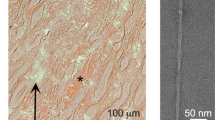

Severe amyloid deposition was histologically observed in the kidneys and livers of all 5 cats. There was severe deposition in the liver, mainly in the space of Disse, with no obvious differences in distribution among individuals (Supplementary Fig. 1). In the kidney, all cases showed amyloid deposition in glomeruli and interstitial connective tissue in the cortex, as well as diffuse deposition in the tubular interstitium of papilla (Supplementary Figs. 2–6). Cases with severe amyloid deposition in the renal papilla were accompanied by necrosis of the renal papilla. Within the renal medulla, amyloid distribution varied among cases (Table 1). In cases 1 and 2, severe amyloid deposition was observed in the medulla, particularly from the outer stripe of outer medulla (OSOM) to the inner medulla (IM) (Fig. 1, Supplementary Fig. 2 d). These amyloid deposits were primarily observed along the basement membrane of the renal tubules, and the deposition that extended into the lumen caused epithelial cells sloughing (Fig. 1c). In contrast, medullary amyloid deposition was milder in cases 3–5 (Fig. 1b). Amyloid deposits were primarily observed in the perivascular interstitium, where they extended from the basement membrane into the surrounding interstitium in a patchy or smudgy manner (Fig. 1d). These deposits resulted in expansion of the interstitial space. Notably, the changes were mainly in the OSOM (Supplementary Fig. 4). Immunohistochemistry (IHC) revealed that all of the hepatic and renal amyloid deposits were positive for the commercial anti-Pan-SAA antibody, indicating AA amyloidosis (Supplementary Figs. 1–6). Other than amyloid deposition, renal infarction was observed in cases 1, 2, and 4. Case 3 had lymphoma in the kidney and liver.

Amyloid deposition in the renal medulla in case 1 (a, c, e) and case 4 (b, d, f). Cat. (a, b) Amyloid deposits are highlighted by the Congo red stain (CR). Bars, 100 μm. (c) In case 1, amyloid deposition is primarily observed along the basement membrane of the renal tubules and causes epithelial cell sloughing. Bar, 50 μm. Inset: Amyloid deposits exhibit yellow-green birefringence under polarized light. CR. (d) In case 4, amyloid deposition extends into the renal tubule interstitium. Inset: Amyloid deposits exhibit yellow-green birefringence under polarized light. Bar, 50 μm. CR. (e, f) Amyloid deposits show moderate immunolabeling. Bars, 50 μm. Immunohistochemistry for Pan-SAA.